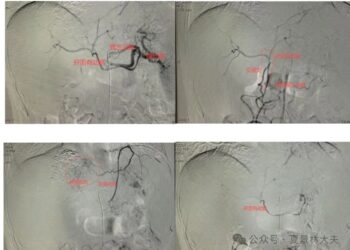

社会 靶免失败、介入无效、肿瘤巨大、重度黄疸,如此棘手的患者是如何绝地逆转的? 作者: 大公文汇融媒体中心 2024/11/30 0 2024年国庆节前,夏教授门诊来了一位特... 阅读全文Details